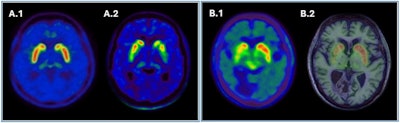

![Pitfalls and artifacts in [F-18] FDG PET imaging. (A) Scan of a patient with central nervous system drug interference shows cortical hypometabolism that could mimic an AD pattern, but with thalamic hypometabolism characteristic of this interference. (B) Scan of a patient with a right frontoparietal ischemic antecedent (arrow), showing a diaschisis of the contralateral cerebellum (arrow) due to disruption of the corticospinal tract. (C) An example of a PET scan with motion artifacts.](https://img.auntminnieeurope.com/files/base/smg/all/image/2025/02/2025_02_13_mol_insider_Figure_5.67ad30bfe2686.png?auto=format%2Ccompress&fit=max&q=70&w=400) Pitfalls and artifacts in [F-18] FDG PET imaging. (A) Scan of a patient with central nervous system drug interference shows cortical hypometabolism that could mimic an AD pattern, but with thalamic hypometabolism characteristic of this interference. (B) Scan of a patient with a right frontoparietal ischemic antecedent (arrow), showing a diaschisis of the contralateral cerebellum (arrow) due to disruption of the corticospinal tract. (C) An example of a PET scan with motion artifacts.

Pitfalls and artifacts in [F-18] FDG PET imaging. (A) Scan of a patient with central nervous system drug interference shows cortical hypometabolism that could mimic an AD pattern, but with thalamic hypometabolism characteristic of this interference. (B) Scan of a patient with a right frontoparietal ischemic antecedent (arrow), showing a diaschisis of the contralateral cerebellum (arrow) due to disruption of the corticospinal tract. (C) An example of a PET scan with motion artifacts.